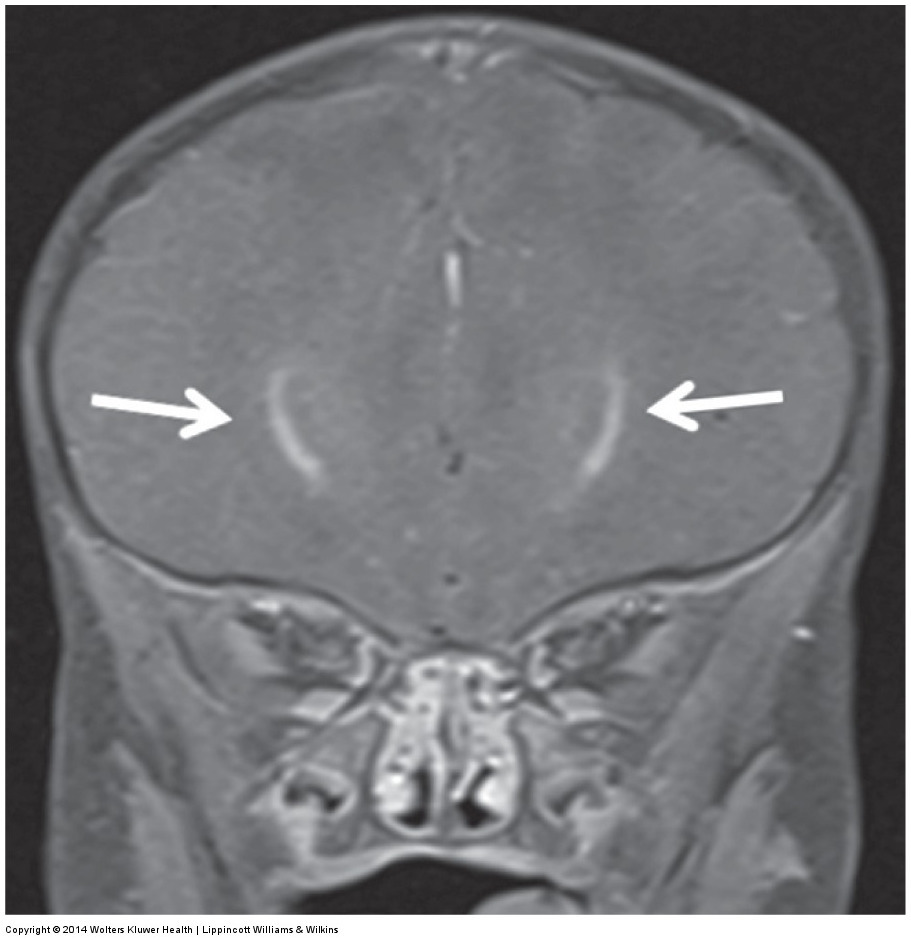

MRI shows asymmetric parietal cortical atrophy, sometimes with associated hyperintensity of the white matter on T2W images.

Axial FLAIR image shows striking asymmetric cortical parietal atrophy in a patient with CBD